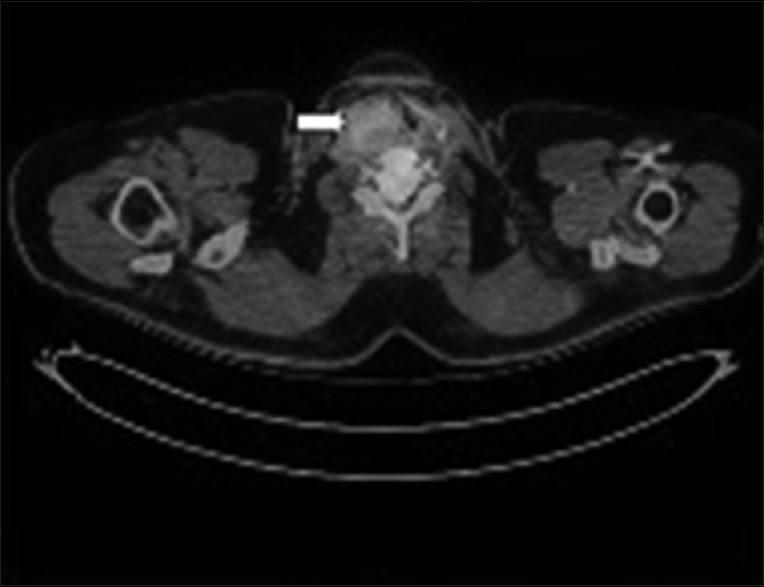

18-Flourodeoxyglucose (FDG) positron emission tomography-CT scan showed an ill-defined nonavid to subtly FDG-avid enhancing soft tissue mass [Figure 1] arising from right lobe of thyroid gland ~3.3 cm × 4.4 cm × 6.7 cm with destruction of adjacent thyroid cartilage and narrowing of airway. Few subcentimetric nonavid to subtly FDG-avid bilateral level IB, II and right Level IV and VI lymph nodes were present.

| Figure 1:Shows an fluorodeoxyglucose-avid enhancing mass arising from right lobe of thyroid (white arrow) causing thyroid cartilage destruction with narrowing of the airway